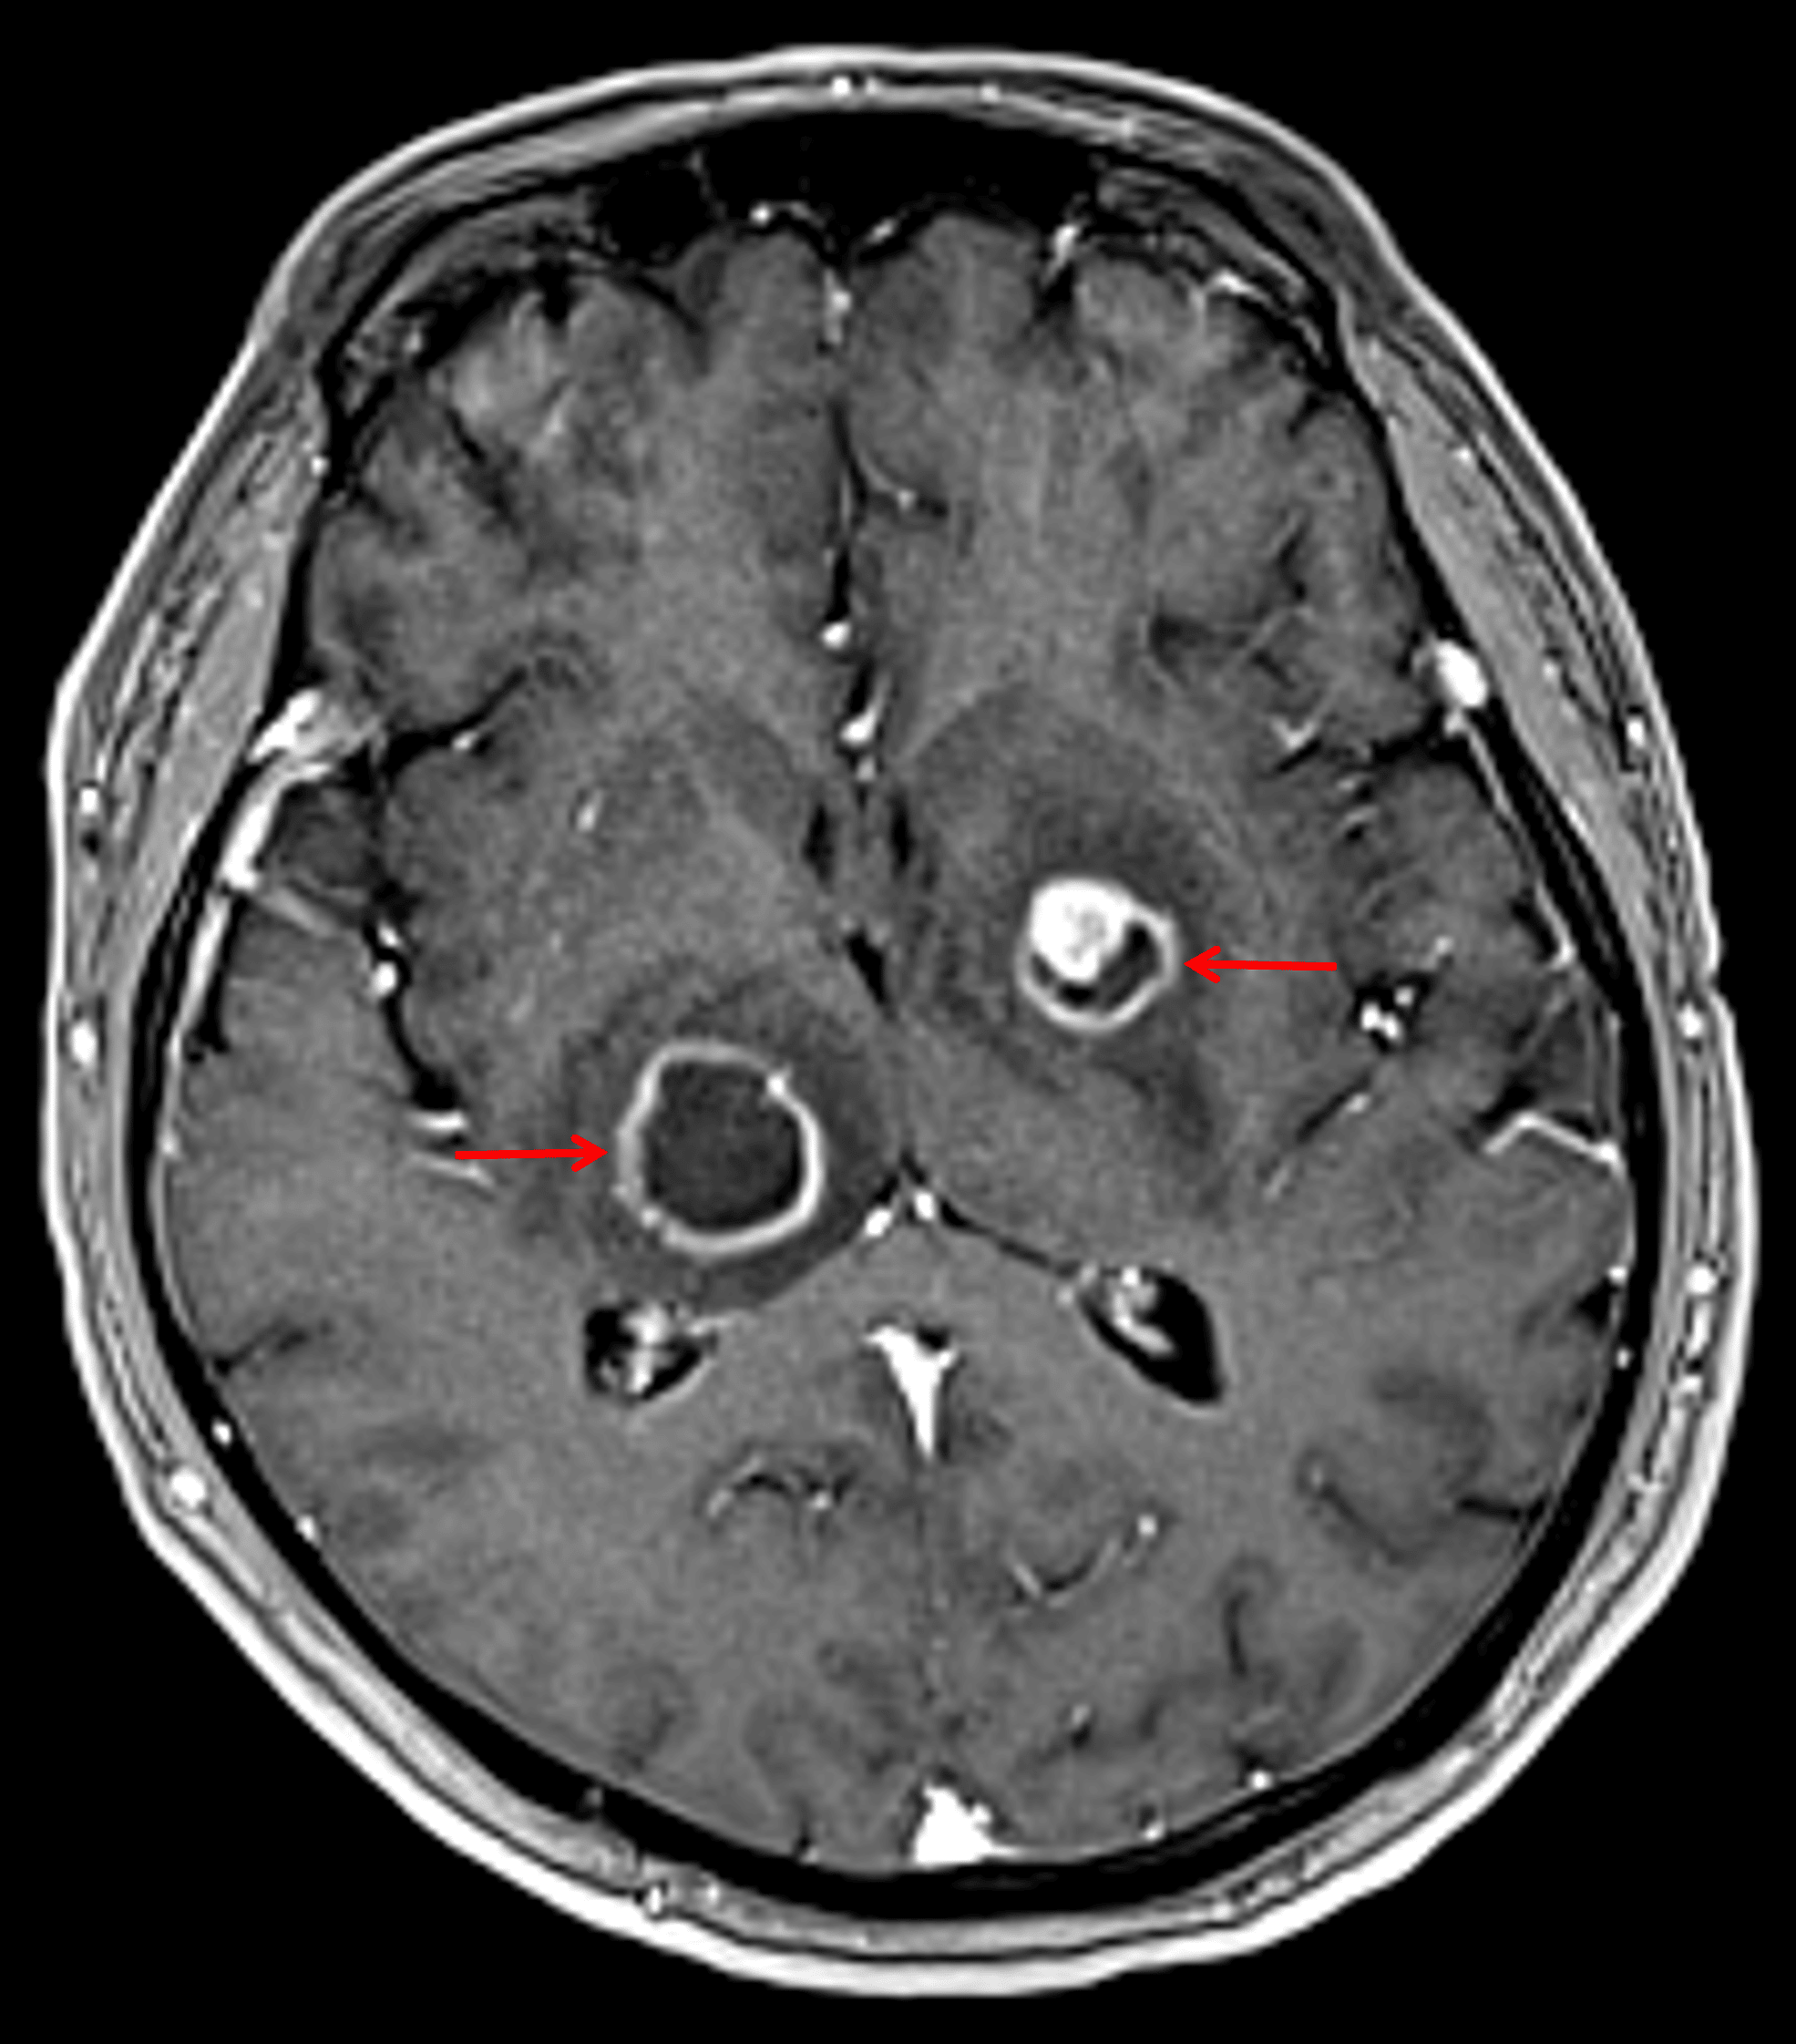

- Peripherally enhancing lesions measuring up to 2.1 cm in the right thalamus and 1.5 cm in the left lentiform nucleus

Peripherally-enhancing lesions in the right thalamus and left lentiform nucleus (red arrows).